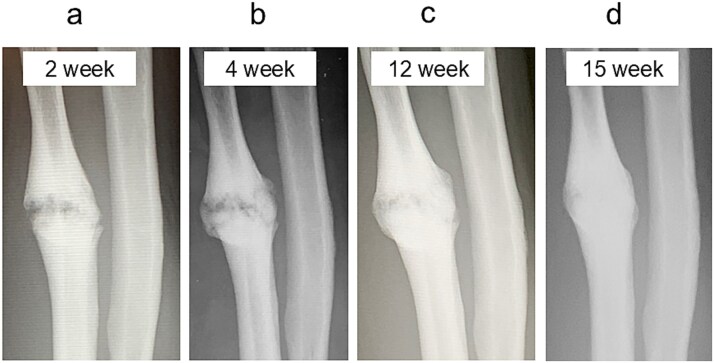

前驱疗法,包括注射高渗葡萄糖来刺激生长因子释放和促进组织愈合,最近作为一种难治性肌肉骨骼疾病的再生治疗得到了关注。我们报告一位54岁的男性,在空手道损伤后出现疼痛的尺干不愈合。保守治疗12个月后失败,患者出现持续性疼痛(数值评定量表[NRS]评分6)。超声引导下使用30%葡萄糖溶液进行前驱治疗,每2-3周进行5次。4周时发现骨痂形成,疼痛完全缓解(NRS评分0),患者在12周时恢复空手道训练。影像学证实15周愈合,无需固定或手术。这个病例强调了前驱疗法作为一种微创和有效的手术治疗疼痛性骨不连的替代方法的潜力。

Prolotherapy, involving hypertonic dextrose injections to stimulate growth factor release and promote tissue healing, has recently gained attention as a regenerative treatment for refractory musculoskeletal conditions. We report a 54-year-old man with a painful ulnar shaft nonunion after a karate injury. Conservative treatment failed over 12 months, and he presented with persistent pain (numeric rating scale [NRS] score 6). Ultrasound-guided prolotherapy using a 30% dextrose solution was performed in five sessions at 2-3 week intervals. Callus formation was noted at 4 weeks, pain completely resolved (NRS score 0), and the patient resumed karate at 12 weeks. Radiographic union was confirmed at 15 weeks without immobilization or surgery. This case highlights prolotherapy's potential as a minimally invasive and effective alternative to surgery for painful nonunion.